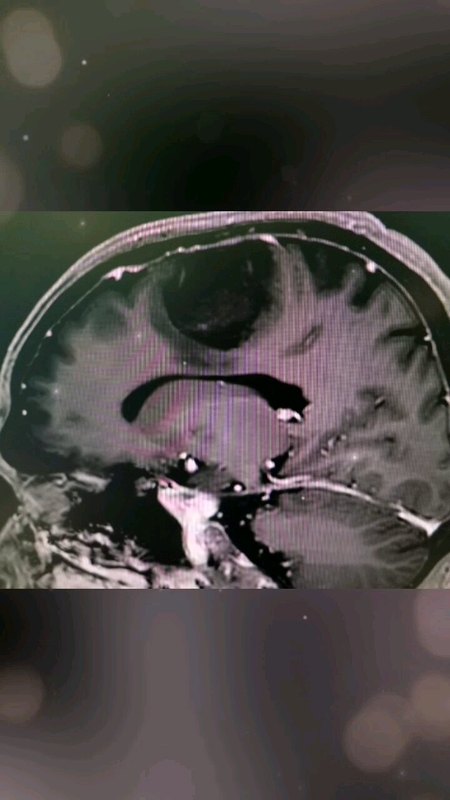

手术切除巨大胶质母细胞瘤,挽救患者生命

孟肖利副主任医师 医科院肿瘤医院 神经外科